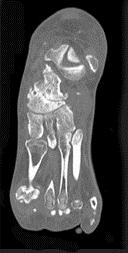

问题 男,68岁,脚行走时疼痛,无红、肿、热、痛,结合图像,最可能的诊断是 ( )

选项 A、骨嗜酸性肉芽肿 B、骨肉瘤 C、骨结核 D、骨转移瘤 E、骨性关节炎

答案 E